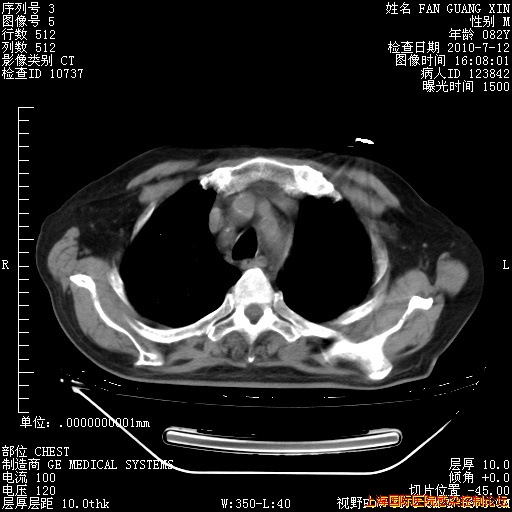

今天复查CT

今天CT

整整相隔30天的肺部CT好像有所好转啊。甲强龙减量第3天,需要观察体温。

海管,自昨日你和我通完话后,不知您岳父消化道症状有无缓解?体温怎样?阅读7.12日胸部ct,个人认为目前激素治疗是有效的,甲强龙减量是适宜的。因在抗痨治疗,需密切观察肝功、肾功能和血常规。不过,老年、长期住院和大量使用激素,很担心菌群失调发生